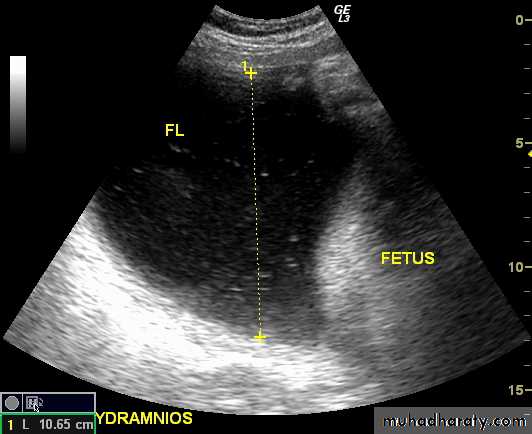

Poly hydraminous :

Poly hydraminos refers to a situation where the amniotic fluid volume is more than expected for gestational age.

It is generally defined as:

amniotic fluid index (AFI) > 25 cm

largest fluid pocket depth (maximal vertical pocket (MVP)) greater than 8 cm

overall amniotic fluid volume larger than 1500-2000 cc3